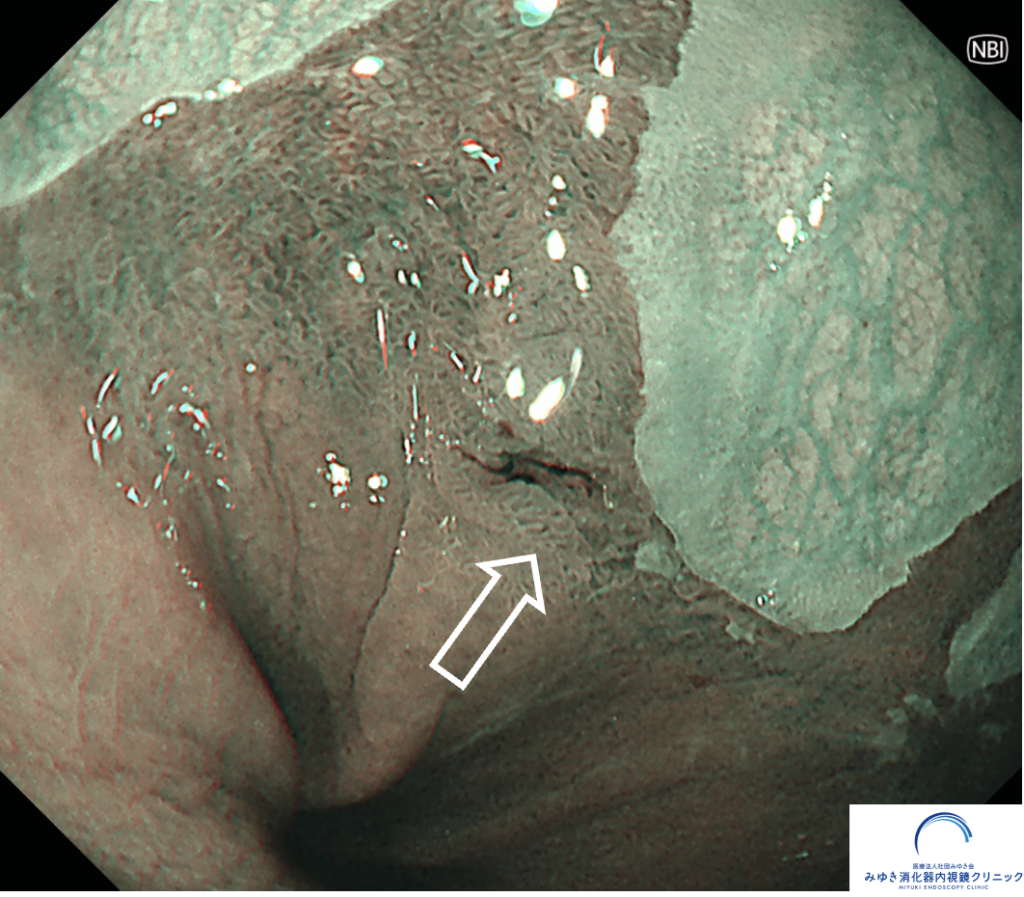

ある検査の際、バレット食道の部分にごく小さな「へこみ(陥凹)」と軽い出血が見つかりました。

NBI観察

<特殊光(NBI・TXI)での精密観察が重要>

NBI(狭帯域光観察)

TXI(構造・色調強調観察)

といった 画像強調内視鏡(IEE) を組み合わせて、粘膜の微細な血管・表面構造を詳細に観察します。

こうした特殊光観察は、数mmレベルの早期バレット食道がんの発見に非常に有用 です。